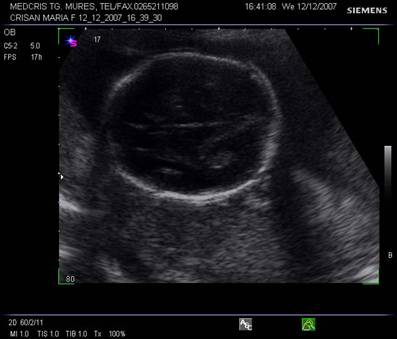

Fig. nr. 151 Planul III de sectiune transversala a craniului fetal.

Planul

IV pune in evidenta ecoul liniei de mijloc, partial vizibil si mezencefalul

superior.

Fig. nr. 152. Planul IV de sectiune transversala